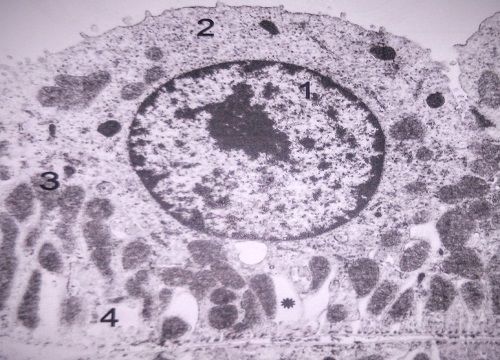

Hepatocyte